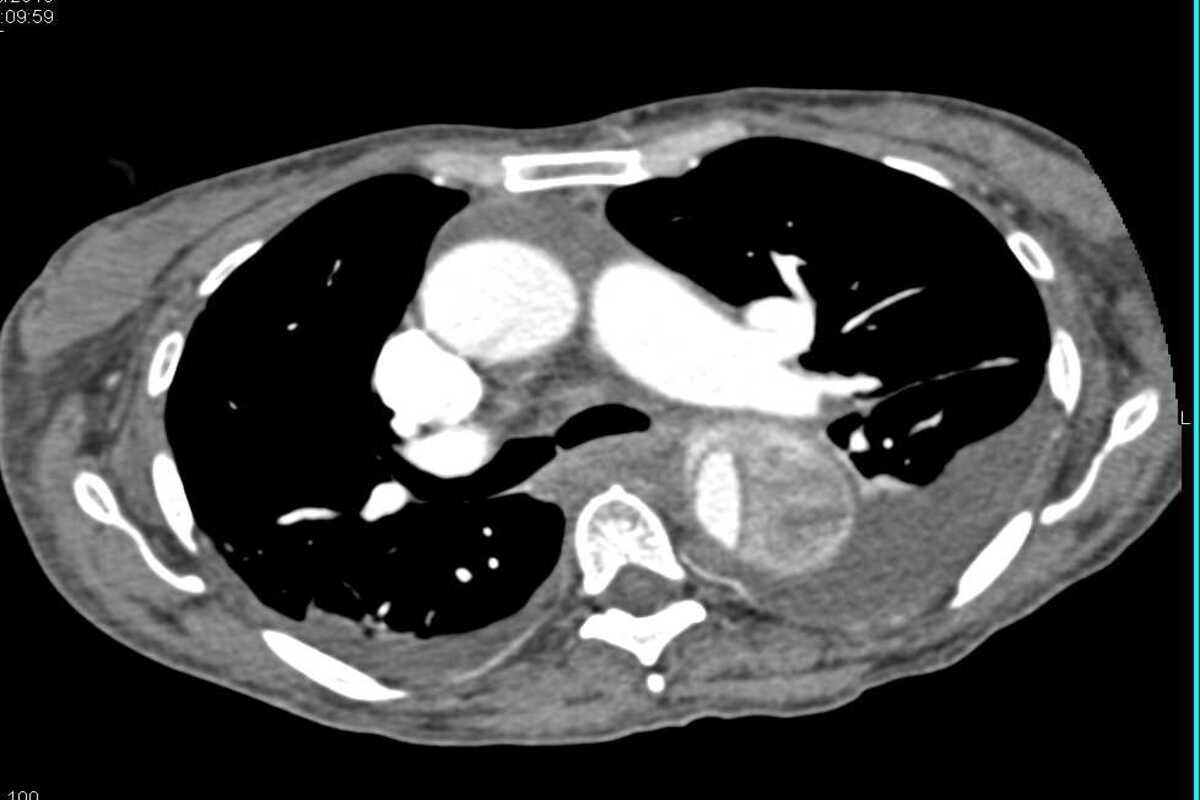

Нейробластома у детей – это опухоль, которая поражает симпатическую нервную систему и формируется из нейробластов – зародышевых нервных клеток. В 97% случаях патология развивается у пациентов, которые не достигли 15-летнего возраста.

Процесс выздоровления при нейробластоме зависит от ранней диагностики и лечения, которое часто затруднено из-за отсутствия клинических проявлений на ранних этапах. Обычно патологический процесс выявляется при достижении новообразованием больших размеров. Пациенту назначается индивидуальная схема лечения.